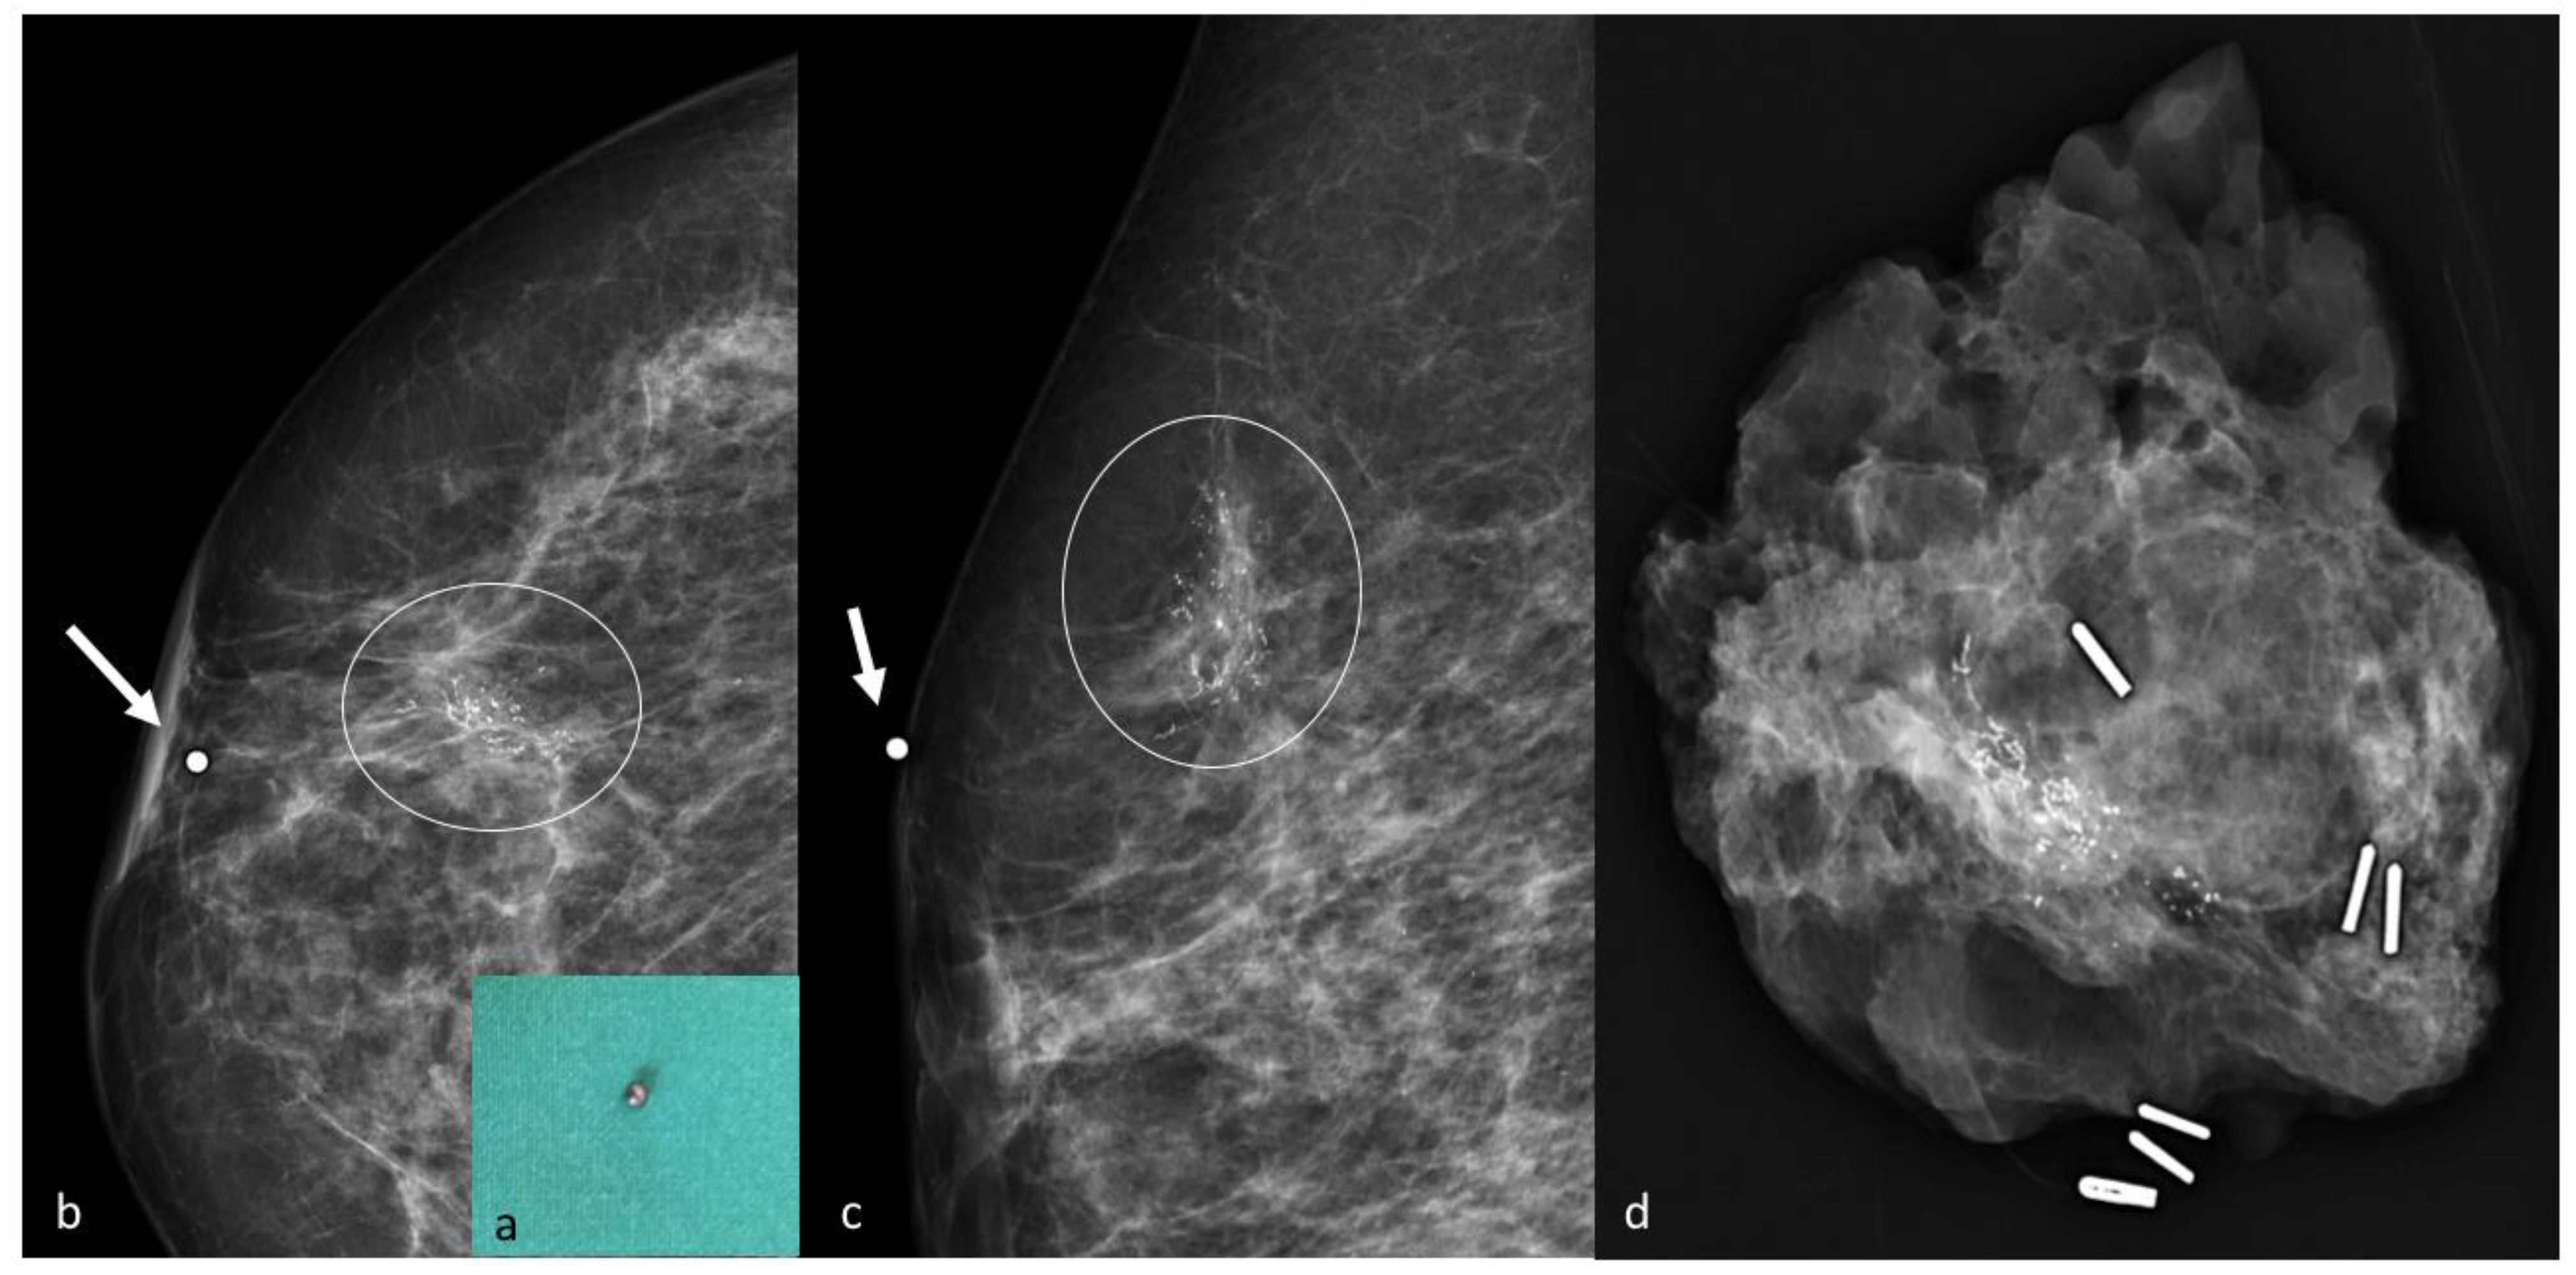

5. Radioactive Seed Localization